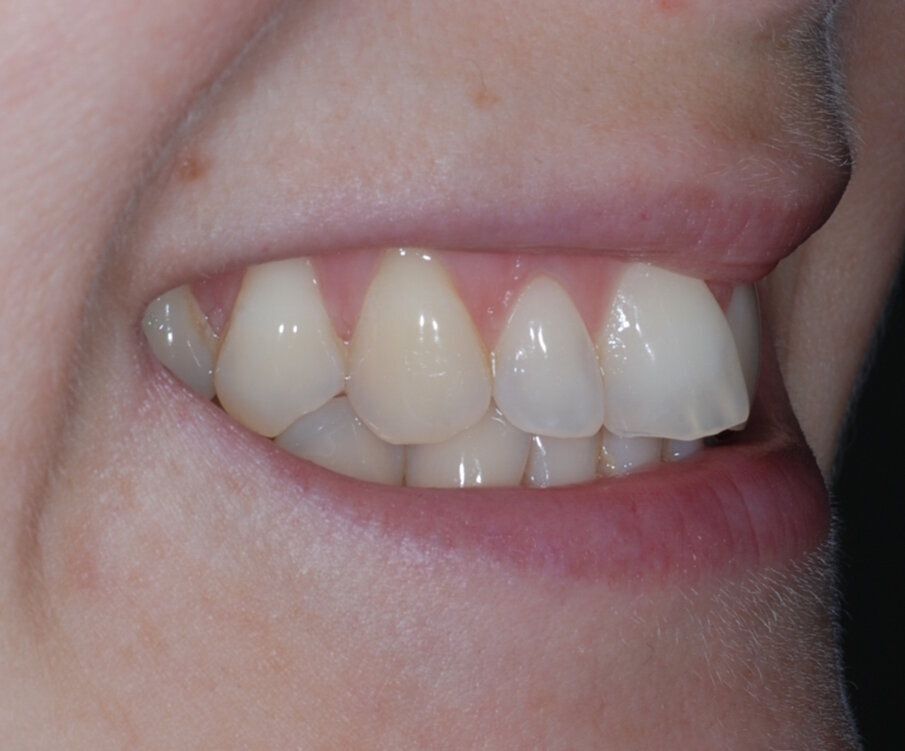

Fig. 15: Post treatment anterior

Fixed retainer bonded followed by composite bonding of UR1 and UL1 using the reversed Fixed retainer bonded followed by composite bonding of UR1 and UL1 using the reversed triangle technique. The benefits of this technique include: • Affordable • Ethical (preserves tooth structure) • Aesthetic • Simple • Complements alignment therapy

Afterwards, the restoration was polished with both flexi disks and Mini FlexiBuff with Enamelize polishing paste. At the end of this appointment, new impressions were taken for new bleaching trays and an Essix retainer. |

The patient was very satisfied with the results, especially the fact I was able to improve her smile without affecting the integrity of the enamel. I sent before and after images to the patient at the end of her treatment pathway so that she could see the difference, and she was amazed at how much the aesthetics of her teeth had changed. I was also very happy with the outcome – with the help of the IAS Academy and digital planning tools, treatment was safe and predictable.